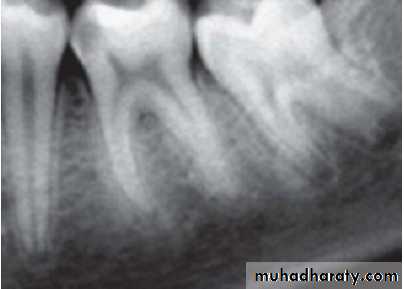

2. Radiographic findings:

– May show depth and extent of caries.– Periapical area shows normal appearance but a slight widening may be evident in advanced stages of pulpitis.

• Radiographic changes show:

– Chronic apical periodontitis in longstanding cases.

– In young patients, low grade longstanding irritation stimulates periapical bone deposition, i.e. condensing osteitis. Radiograph shows areas of dense bone around apices of involved teeth.

Radiographic Features

• Mostly discovered on routine radiographic examination• The earliest change in the periodontal ligament is found to be thickening of ligament at the root apex

• Lesion may be well circumscribed or poorly defined

• Size may vary from small lesion to large radiolucency exceeding more than 2 cm in diameter.

• Some amount of root resorption has been reported.